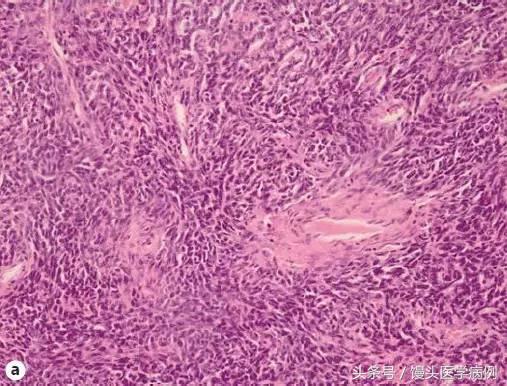

图 4 a 颗粒细胞瘤组织学切片(HE 染色法 250 倍);b 颗粒细胞瘤细胞学涂片,可见到中等细胞涂布,散落的乳头状结构及腺状结构,大量落单卵圆细胞,有凹槽,胞核小,可见到卡埃二氏小体,未见到核分裂象(巴氏染色法 250 倍)

图 5 a 颗粒细胞瘤组织学切片(HE 染色法 250 倍);b 颗粒细胞瘤细胞学涂片,可见到大量落单的圆形或梭形小细胞及散在的肥大细胞(瑞氏染色 400 倍)